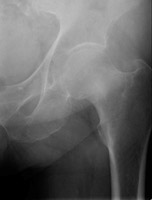

- Click on the image for a larger versionDAP radiograph of the right hip. This shows a Garden III fracture of the proximal femur.